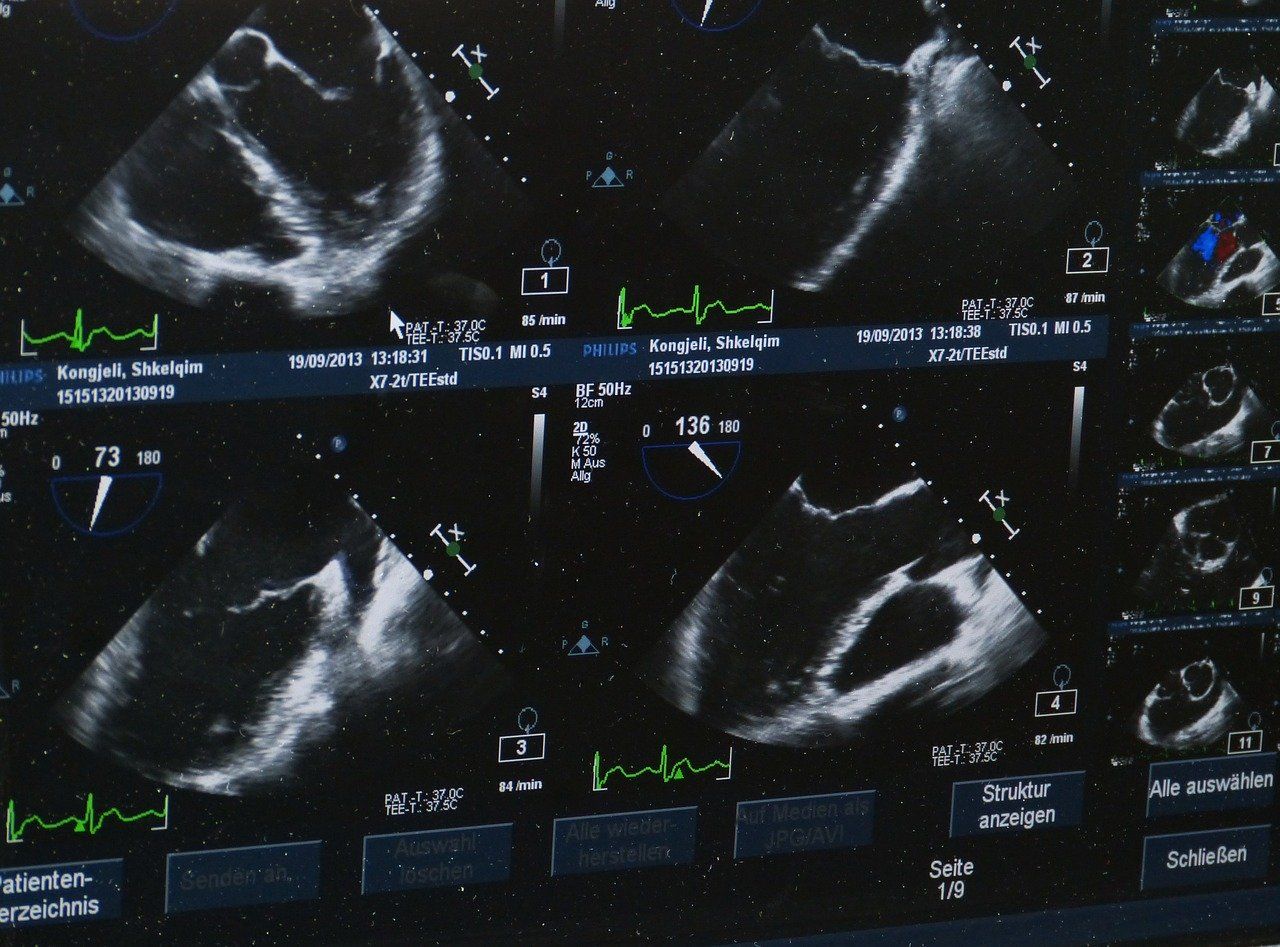

Image is Everything

In addition to the report requirement, we want to remind you that you cannot get paid for your USG service if you do not retain the image. This can be done by hard copy or digitally, but it must be present and available. The Radiology Guidelines section of CPT 2019 clearly indicates that all supervision and interpretation imaging codes require "image documentation in the patient's permanent record."

I recall visiting with doctors at a certain anesthesia group years ago who insisted that they were retaining the USG images digitally, only to find out later that the digital images were not being associated with the patients in question. In other words, the images were present but simply not tied to any particular patient! This should serve as a reminder to all groups that they should confirm that their USG images are (a) being retained, AND (b) able to be connected back to the patients for whom the services were performed. It does no good to retain images if they cannot be connected to the patient in the event of an audit.